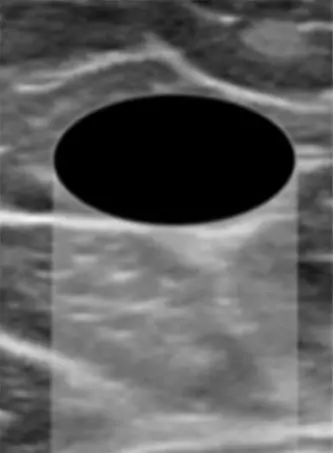

낭종(Cyst)

무에코 패턴

타원형 또는 원형

경계가 뚜렷한 가장자리

수평 방향

후방 에코 증강

석회화 없음